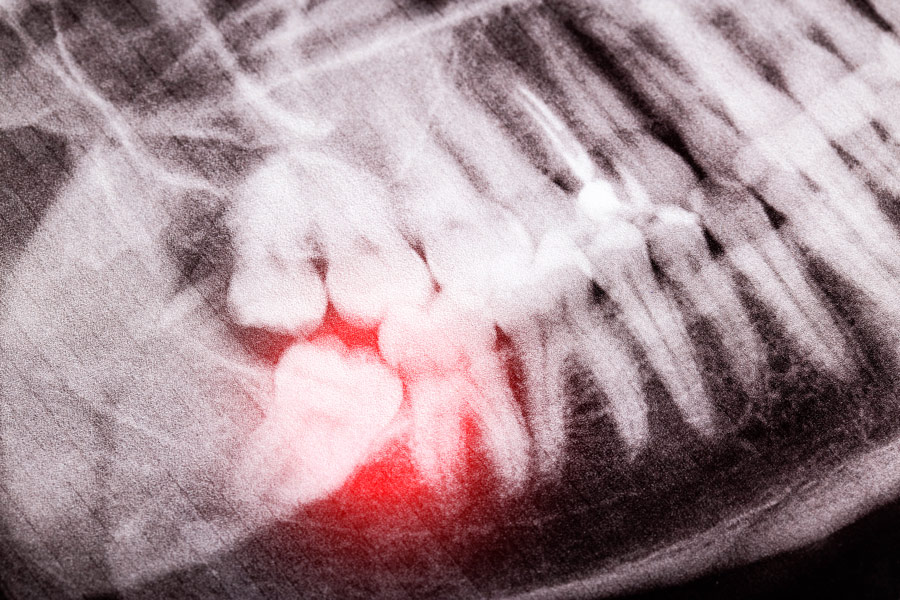

During an oral examination, your surgeon will review X-rays and evaluate the position and development of your wisdom teeth. This allows us to identify existing concerns and anticipate potential issues before they become more serious.

Fluid-filled cysts can develop around impacted wisdom teeth due to ongoing pressure within the jaw. These cysts may grow slowly and damage surrounding bone and nearby teeth. Early detection and treatment help prevent more extensive complications.